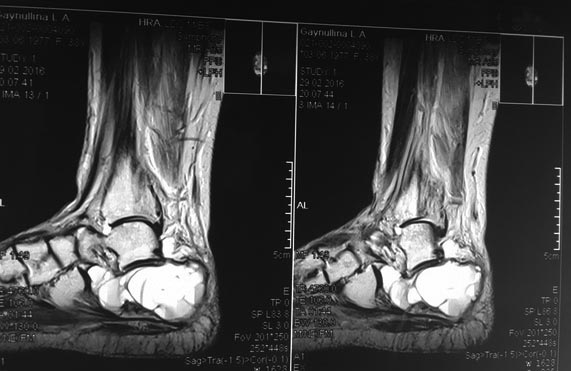

Пациентка с большой аневризмальной костной кистой пяточной кости.

Пациентка Г., 38 лет. 1,5 года назад появились боли в левой пяточной

кости. Болей в покое и ночных болей нет. 08.09.15 операция: экскохлаеция

аневризмальной костной кисты, пластика деминерализованными костными

трансплантатами. По данным МРТ (29.02.16) костной

перестройки нет, вероятно произошел выход содержимого кисты в

пространство позади ахиллова сухожилия.